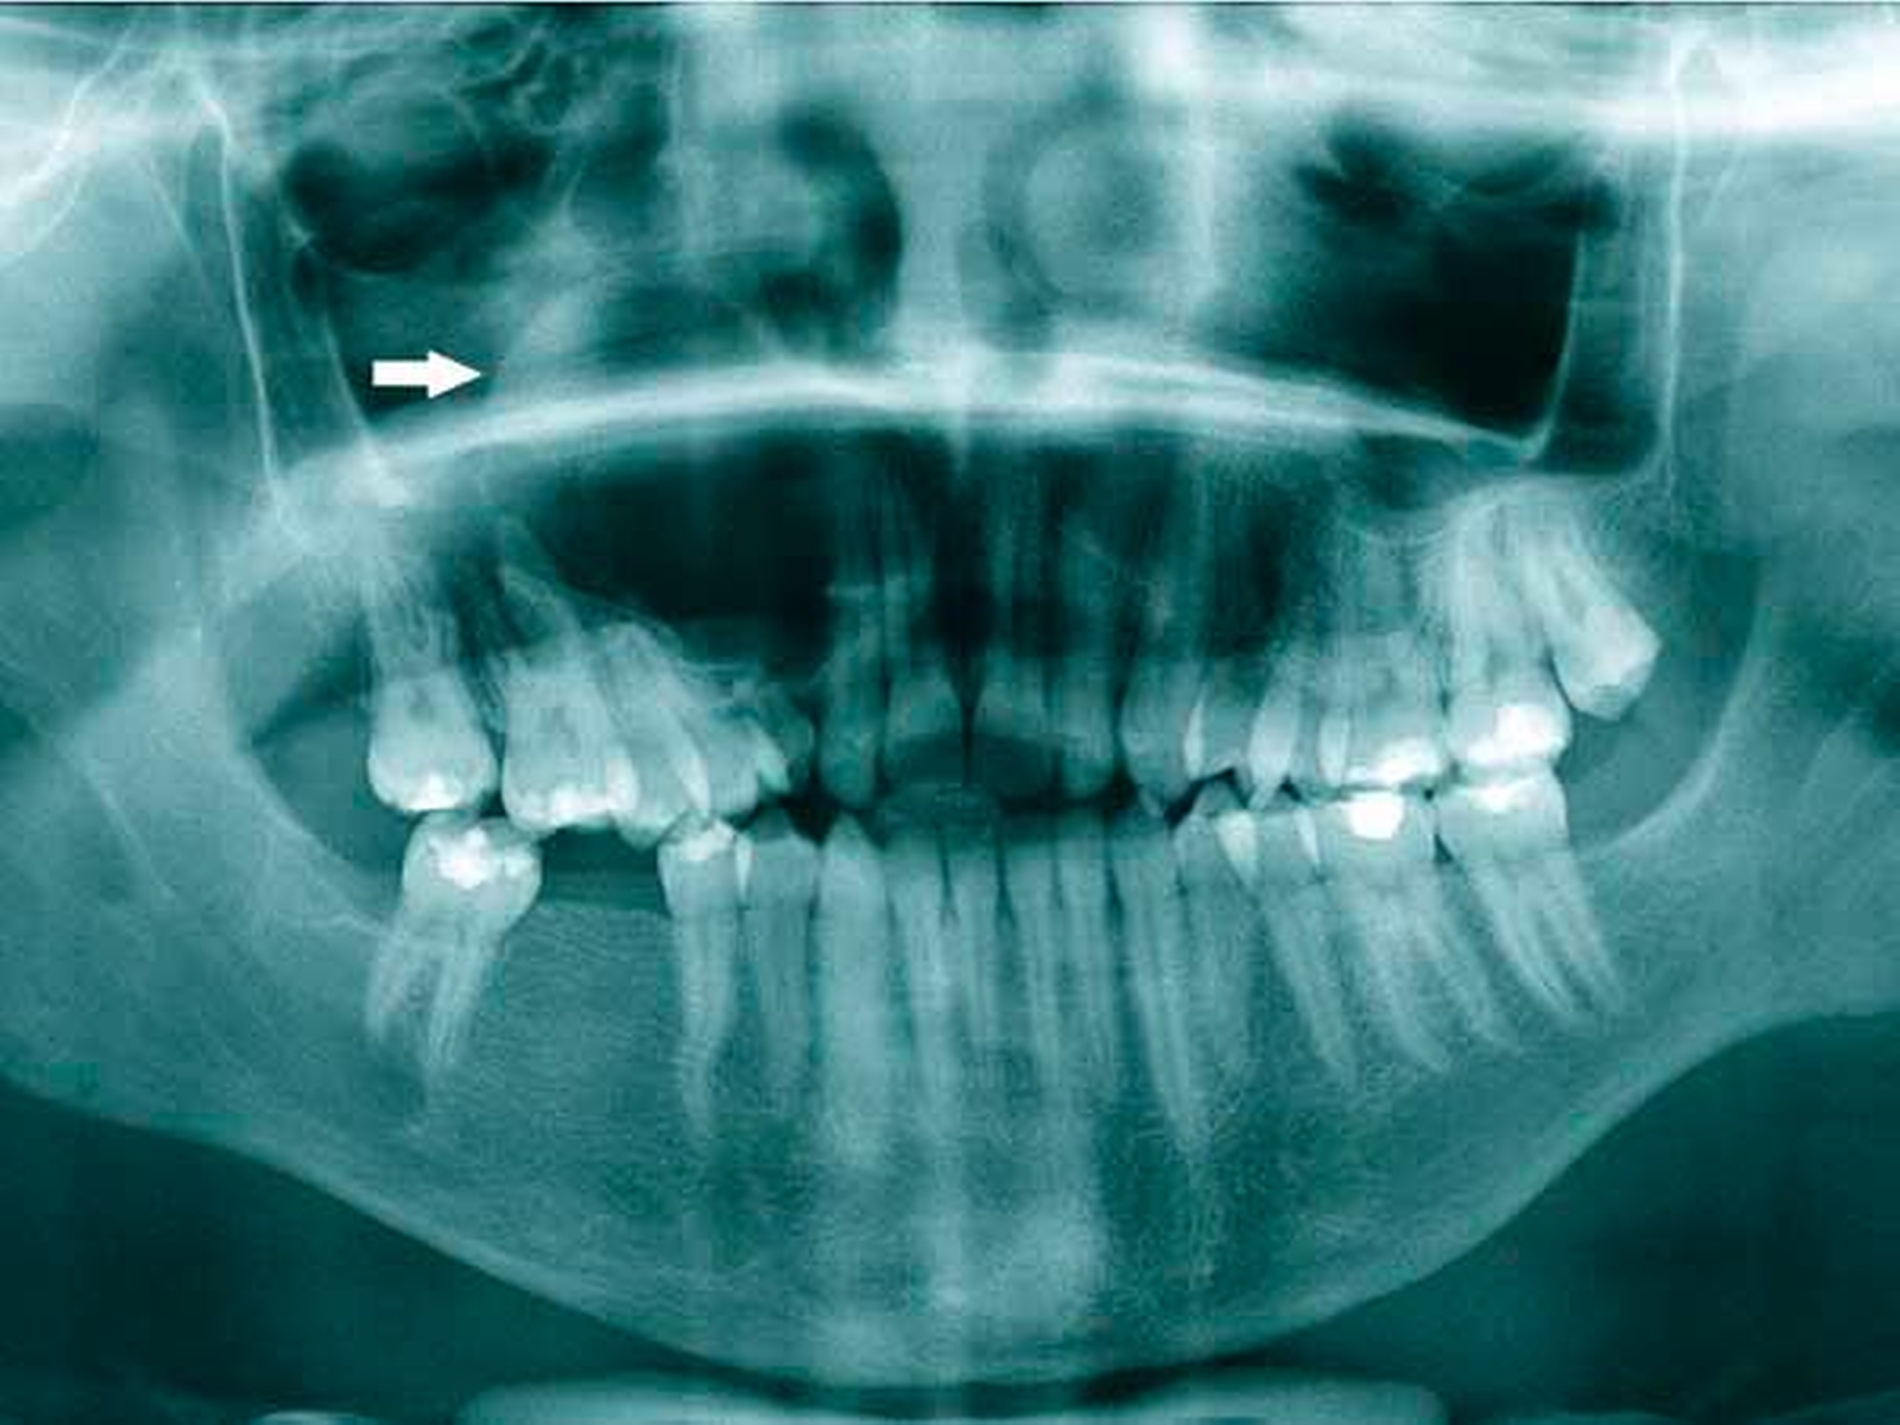

Ein 17-jähriger Patient wurde mit einer odontogenen Zyste im rechten Oberkiefer überwiesen (Abbildung 1). Bereits fünf Jahre zuvor waren bei ihm multiple Keratozysten entfernt und der Verdacht auf ein Gorlin-Goltz-Syndrom geäußert worden, dieser wurde jedoch nicht weiter abgeklärt. Anamnestisch lagen bisher keine Basalzellkarzinome vor.

Zur weiteren Beurteilung der Ausdehnung des Befunds wurde eine Nasennebenhöhlenaufnahme veranlasst (Abbildung 2). Darin zeigte sich eine deutlich sichtbare Verkalkung der Falx cerebri, was den klinischen Verdacht eines Gorlin-Goltz-Syndroms nach den Evans-Kriterien (Tabelle 1) [Evans et al.] bestätigte. Ein weiteres auffälliges Merkmal: ein vergrößerter Augenabstand (Hypertelorismus). Weitere, angeborene Fehlbildungen lagen nicht vor, die Familienanamnese war negativ.

Unter Intubationsnarkose erfolgte die Zystektomie mit Knochenkürretage. Der histopathologische Befund bestätigte den Verdacht einer Keratozyste. Der Patient befindet sich nun in einem engmaschigen Nachsorgeprogramm, ebenso erfolgen regelmäßig dermatologische Vorstellungen.